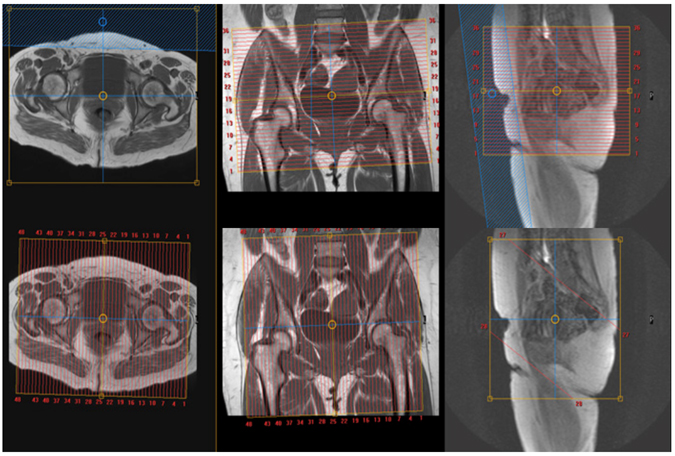

MRI Pelvis WO MSK Protocol

| Plane | Weighting | Mode | Slice | Gap | FAT SAT | FOV | Notes |

|---|---|---|---|---|---|---|---|

| AXIAL | T1 | TSE | 5-6 mm | 1mm | None | 30cm | Entire SI Joints To Lesser Trochanters |

| AXIAL | T2 SPAIR | TSE | 5-6 mm | 1mm | SPAIR | 30cm | Entire SI Joints To Lesser Trochanters |

| COR | T1 | TSE | 5-6 mm | 1mm | None | 30cm | Sacrum Through PS (Skin to Skin) |

| COR | T2 STIR | TSE | 5-6 mm | 1mm | STIR | 30cm | Sacrum Through PS (Skin to Skin) |

| SAG | T2 SPAIR | TSE | 5-6 mm | 1mm | SPAIR | 30cm | Cover Iliac crests through lesser trochanters |

| SAG (optional) | T1 | TSE | 5-6 mm | 1mm | None | 30cm | Optional: Cover iliac crests through lesser trochanters |